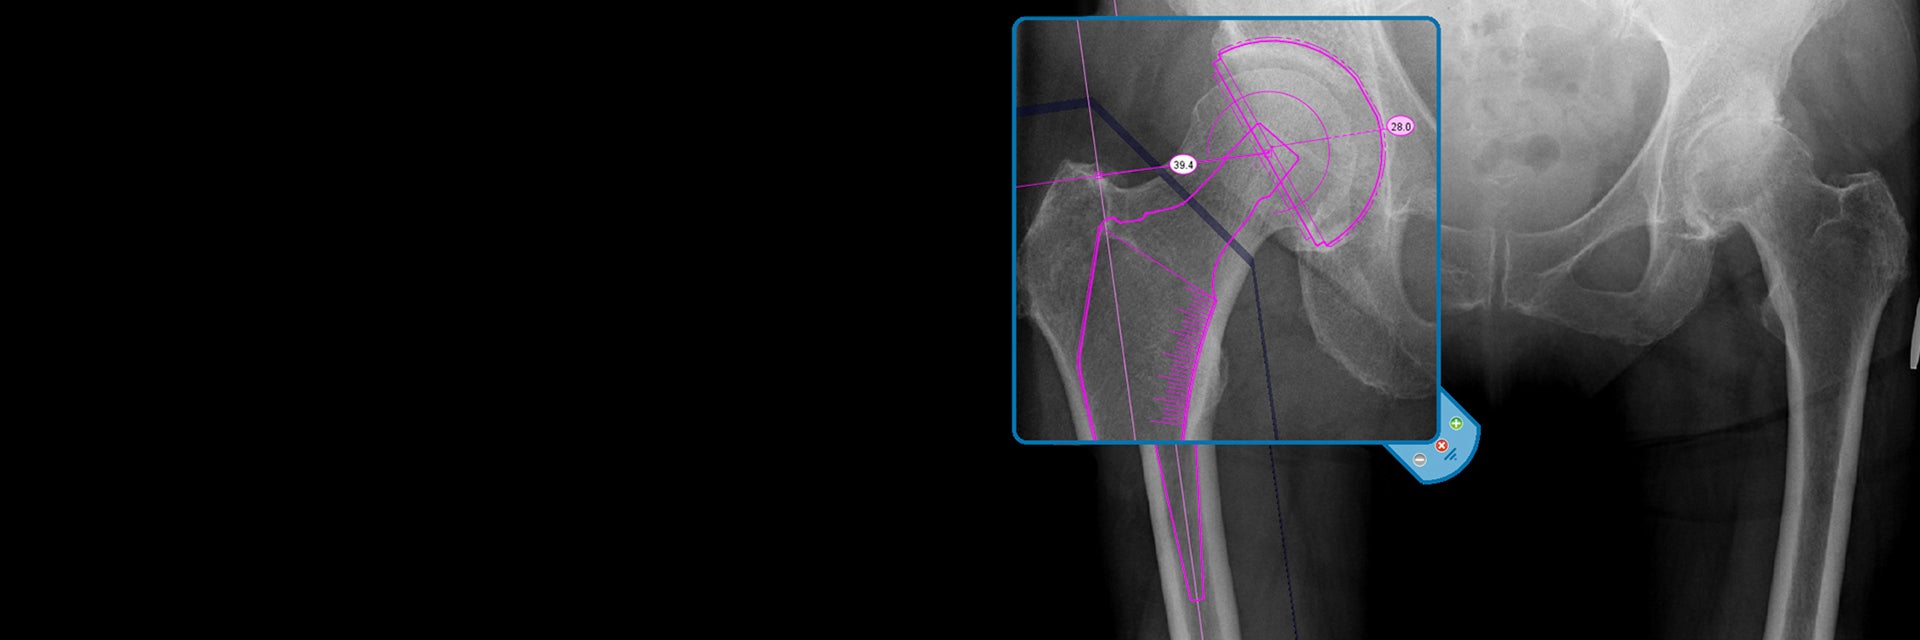

All the x-ray images were templated by Dr. Shaw using Materialise OrthoView Digital Pre-operative Planning Software. The resulting images and reports were saved back to the PACS and a copy of the templated sizes printed on what Dr. Shaw refers to as a “shopping list” or list of prostheses required. This list was used to collect the prostheses most likely to be needed for the surgery that day. In some cases, two optional sizes were recorded when the templating was between two sizes. A clinical decision was then taken at the time of surgery to identify the best option for the patient.

The component sizes recorded were stem size, stem offset, neck length for the 28 mm head, acetabular size and cement restrictor plug size. The neck length and plug sizes were roughly templated and usually two sizes were recorded on the shopping list because Dr. Shaw believes that these component sizes are best judged at the time of surgery.

As in the table above, the templated Exeter hip stem offset matched the actual measurement in 100% of cases (all 39). Dr. Shaw commented that “in only 2 cases did I feel it necessary to hedge my bets by noting 2 possible sizes at the time of templating.”

The results also show that the Exeter hip stem size correlated exactly in 85% of cases, and in the other 15% the size used was 1 size different. Again only 2 cases had two options recorded from the templating. Of the 6 mismatches, 3 were oversized and 3 undersized.

Acetabular sizing was an exact match in 87% of cases, with 7 cases recording two options. All discrepancies were 1 size out. Of the 5 mismatches, 2 were undersized, and 3 oversized.